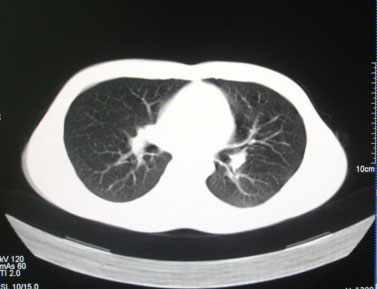

标题: CT26938:单发肺窗

病人17岁。咳嗽伴血丝痰2年?外院x片示左上肺椭圆形影,疑胸腺瘤

左肺尖见占位,建议上传纵隔窗及向上扫描。

左上纵隔占位性病变?